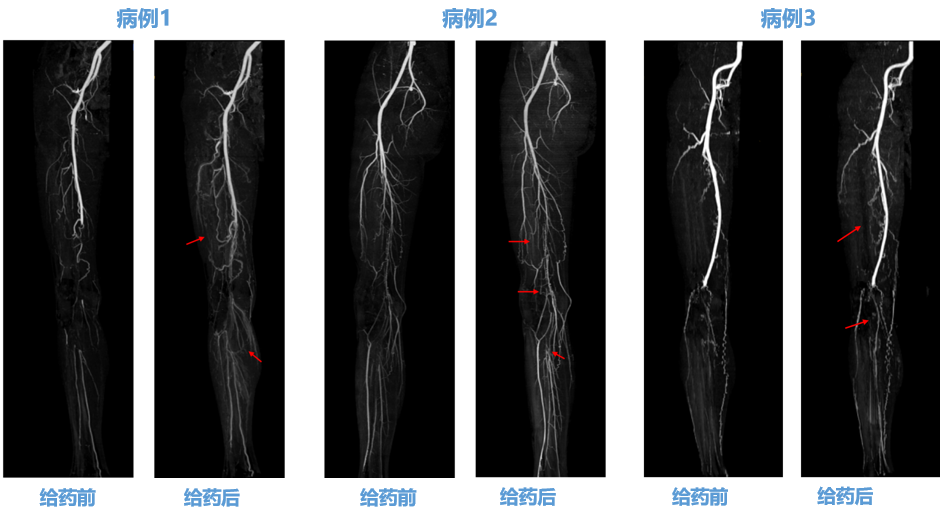

★ pUDK-HGF 给药前后新生血管情况